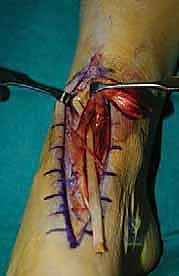

5. إعادة توجيه وتر EHL (Tendon Routing)

وهي خطوة حاسمة لنجاح البيوميكانيكا. يتم تمرير وتر EHL المستخلص عبر الغمد الخاص بوتر الظنبوب الأمامي الممزق، أو تحته، لضمان أن يكون خط الشد (Line of Pull) مطابقاً تماماً للوتر الأصلي، مما يضمن رفع القدم بشكل متوازن دون انحرافها للخارج أو الداخل.

7. ماذا يحدث لإصبع القدم الكبير؟ (معالجة الجذع المتبقي)

بما أننا أخذنا الوتر الذي يرفع إصبع القدم الكبير، هل سيسقط الإصبع؟ لتجنب ذلك، يقوم الدكتور هطيف بإجراء تقنية تُسمى (Tenodesis). يتم خياطة الجذع المتبقي من وتر EHL في وتر العضلة الباسطة القصيرة للإصبع (EHB) أو في وتر الأصابع المجاورة (EDL). هذا يضمن بقاء إصبع القدم الكبير مرفوعاً ومستقراً ولا يعيق المشي.